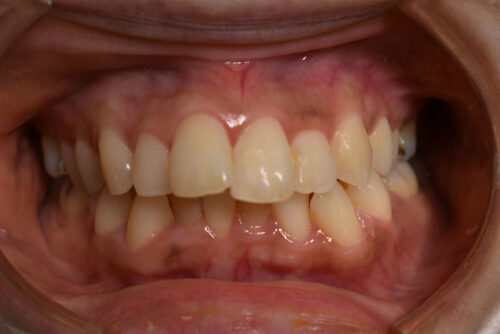

前歯のがたつき(叢生)が気になる方を非抜歯矯正治療で治した症例(ワイヤー9か月)

初診時年齢 39歳 女性

歯のでこぼこ(叢生)

を主訴に

池袋よりひとつ隣駅の東京都豊島区大塚駅すぐの大塚たまみ矯正歯科へ

いらっしゃいました。

奥歯のかみ合わせに 前後的な ずれは ないものの

上下ともに 前歯部に

顕著な 叢生(でこぼこ)が

認められました。